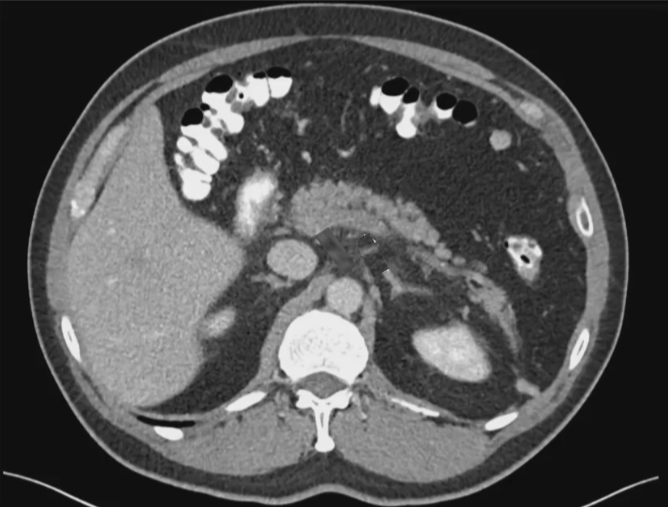

46 岁男性,伴有轻微腹痛和发热症状 诊断出门静脉(PV)和肠系膜上静脉(SMV)存在广泛的、严重的血栓形成。 病史:30 年前因摩托车事故接受脾脏切除手术

PVT(门静脉血栓)可能会导致门静脉高压以及侧支循环的形成以及肠道缺血。 抗凝治疗是常规疗法。然而,仅有 39%(6个月内)的患者能够实现门静脉的完全再通。 在血管内治疗技术方面的经验尚显不足,但这类技术确实提供了颇具前景的治疗方案【Pissier 2010】。 TIPS 与血栓切除术及 CDT 结合使用是治疗急性门静脉血栓形成的一种替代疗法,尤其适用于血栓范围广泛的病例。 有必要开展对比不同治疗方法的前瞻性研究,以明确这些方法的益处。 门静脉血栓形成:让“不可能”的经颈静脉肝内门体分流术成为可能……经脾静脉、肠系膜上静脉和肠系膜下静脉 |